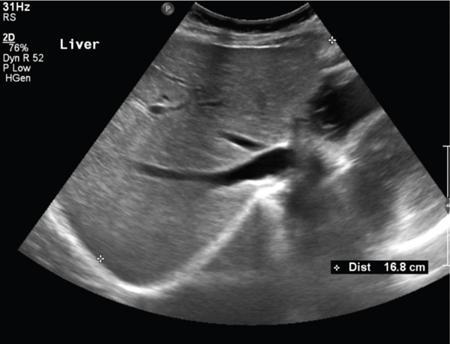

Ritu K. Kashikar, Shrinivas B. Desai Knowledge regarding normal dimensions of organs is important as visceromegaly is the first and often only abnormality in a variety of disorders. The radiologist should also be aware of normal diameters of vessels and ducts because an increase in size is usually a pointer to pathology in the organ. This chapter is a lucid review of normal sizes of organs, vessels, duct and also focuses on which section and location should size be measured to avoid interobserver variation. The liver is the largest organ in the abdomen. Hepatomegaly is a common condition and often the first clinical and imaging feature of various disorders. It is hence imperative for the radiologist to know the normal size and the section on which measurements should be taken. USG is commonly used to measure liver size. The longitudinal view is commonly used to measure liver size. The liver is considered normal in size if on longitudinal scan through the midhepatic line the liver measures 13 cm or less. This is true in approximately 93% individuals Measurement more than 15.5 cm suggests hepatomegaly in 75% cases (Figs. 9.3.1 and 9.3.2) (Table 9.3.1). Hepatomegaly is also suggested by an inferior angle of more than 45 degrees in the left lobe and more than 90 degrees in the right lobe. The normal liver measures approximately 6.5 cm first 3 months of age and reaches a size of 12.5 cm by 10–12 years of age. Liver size can be measured on unenhanced or enhanced CT. On CT the liver measures 10–12.5 cm in the midclavicular line on an average. A liver measuring more than 15.5–16 cm in the midclavicular line is considered enlarged. The midclavicular line measurement is done in coronal plane (Fig. 9.3.3). Another important measurement is the size of caudate lobe. The caudate to right lobe ratio (C/RL) is a measurement used to diagnose caudate lobe hypertrophy and right lobe atrophy which is important in the diagnosis of cirrhosis. The axial section immediately below main portal vein bifurcation is used for measurements. The following lines are drawn on the liver (Fig. 9.3.4). C/RL: In an adult patient of average weight (60 kg), the estimated liver volumes can range from 1024–1302 cm3 (Fig. 9.3.6). USG and Doppler provide important information regarding patency of artery in postoperative/transplant setting. Normal hepatic artery waveform is pulsatile and of low resistance. The normal resistive index measures 0.7. High or low resistivity index (RI) indicated pathology. The measurements of the hepatic arteries bare importance in transplant imaging. The diameter and length of the arteries are best measured on CT angiogram images. Arteries smaller in calibre than 2 mm may be difficult to anatomize. Replaced RHA is often longer in length than standard arteries. The normal diameters of the hepatic arteries are mentioned in Table 9.3.2 (Figs. 9.3.7–9.3.9). The portal venous system is valveless and hence its diameter is influenced by respiratory variations. The portal venous diameter is greatest during inspiration and hence all measurement should be made in this phase (Table 9.3.3). The diameter of portal vein has importance in diagnosing portal hypertension and USG is often used for this purpose. USG also provides other important parameters like flow velocity and volume flow which are relevant in the setting of portal hypertension. The normal portal venous velocity measures 15–18 cm/sec.(Fig. 9.3.10)

Normal usg measurements